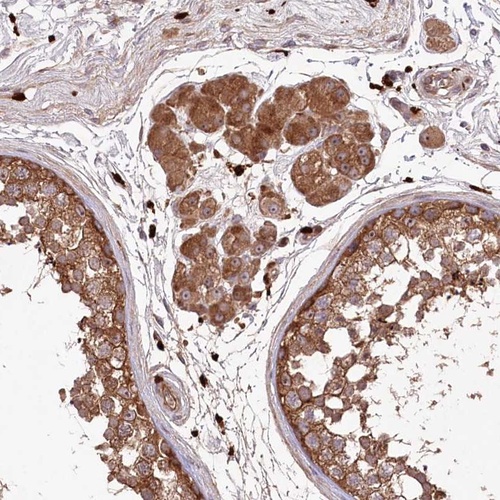

Immunohistochemical staining of human testis shows strong cytoplasmic positivity in cells in seminiferus ducts and Leydig cells.